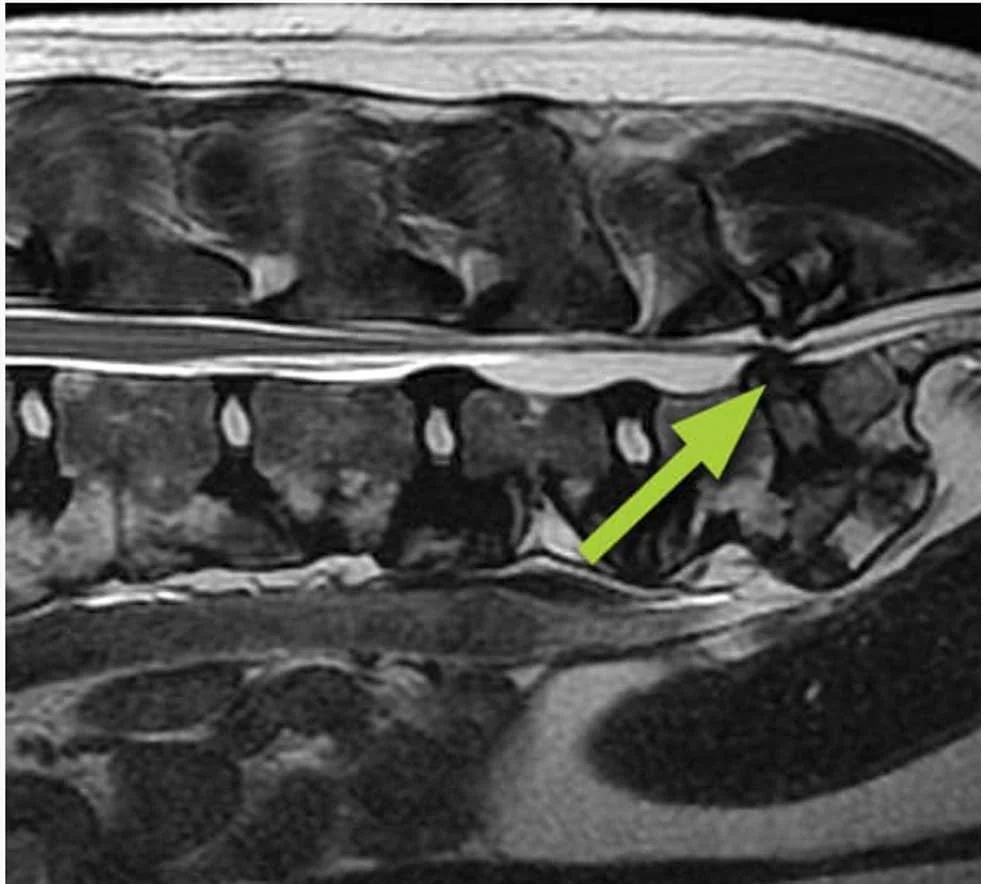

Lumbosacral Disease (Degenerative Lumbosacral Stenosis)

A condition where the lower spine narrows and compresses nerves.

• Common in large, powerful breeds

• Can cause hind limb weakness, pain, and reluctance to jump

• Often develops gradually with age or heavy work

• Weight and conditioning play a significant role